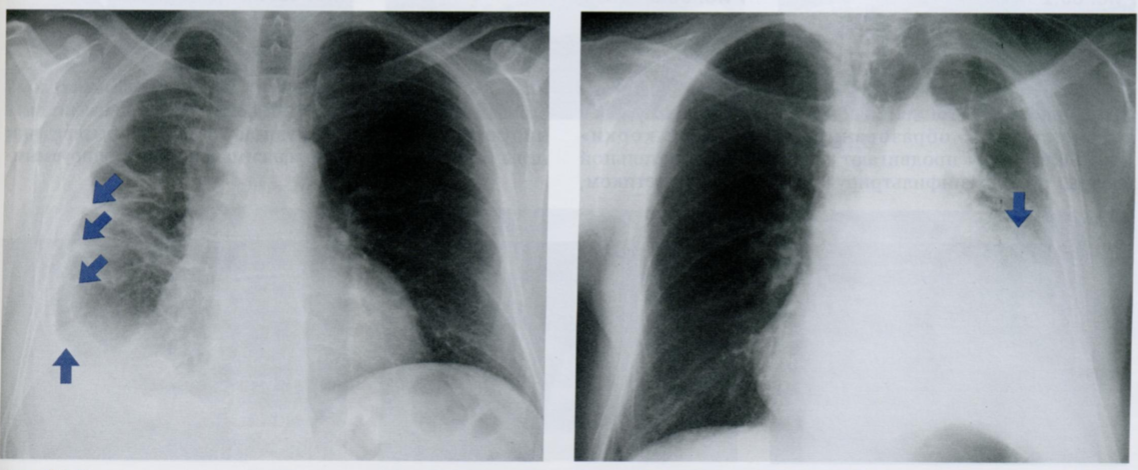

Оцените снимки.

Что из себя представляет фиброз плевры?

Физброз представляет собой грануляционную ткань, которая может вторично обызвествляться.

Плевральный фиброз может развиться как отдаленное последствие лучевой терапии. На снимке определятся подозрительное утолщение плевры в области верхушки (вертикальная стрелка) левого легкого, напоминающее шапку. Фиброз вызвал значительное смещение корня кверху (10) с этой же стороны.

За несколько лет до этого снимка пациентка проходила курс лучевой терапии по поводу рака молочной железы. Кроме того, ей была выполнена восстановительная операция - имплантация протеза молочной железы (контурные стрелки).

На рентгенограмме в БП плевральную «шапку» (стрелка) обнаружить труднее, чем на снимке в ЗПП, из-за наложения различных анатомических структур, что делает более высокой вероятность ошибки.